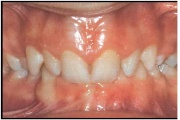

kahepoolse lõhega lapse hambumus

Valehambumus

Hammaste asendianomaaliad on tingitud tavaliselt arenguhäirest.